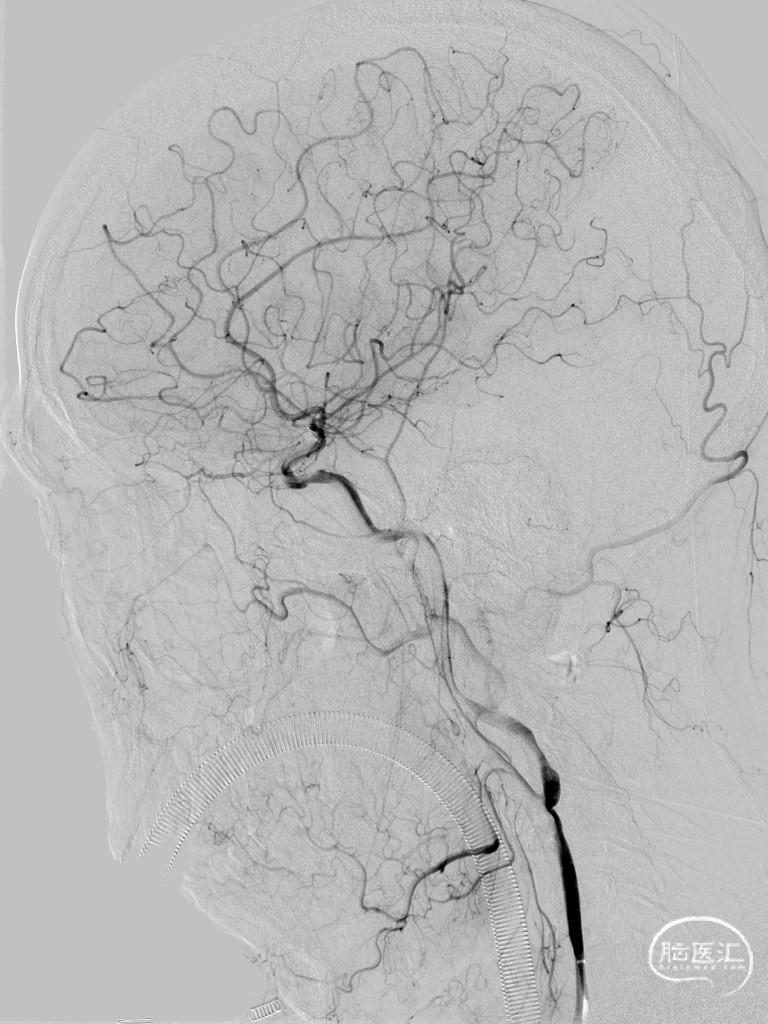

➢ 脑血管造影

经微导丝交换支架微导管,沿微导管送入4*39mm自膨支架至左侧大脑中动脉M1段闭塞病变处,支架成功打开,贴壁良好,支架内血流通畅。

➢ 术后造影